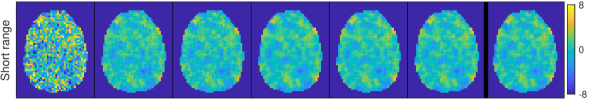

Fig. 2 shows the resulting PPMs for the different spatial priors, with hyperparameters estimated by EB, for the same slice as in Fig. 1. The last column also shows the “true” PPMs obtained by using the A-M with the hyperparameters used to generate the data. We see how the non-spatial GS prior leads to cluttered PPMs which bear little resemblance with the true activity coefficients. We note that the first-order ICAR and M priors, with smoothness , tend to show smaller activity patterns than the second-order priors with , except for perhaps the Short range condition. The differences between the second-order priors ICAR, M and A-M are quite subtle, but for the Weak and Anisotropic conditions ICAR shows some signs of over-smoothing, resulting in slightly larger activity regions compared to the truth. As expected, M and A-M show little discrepancy for the first three isotropic conditions, but for the Anisotropic condition A-M is to some degree closer to the truth.